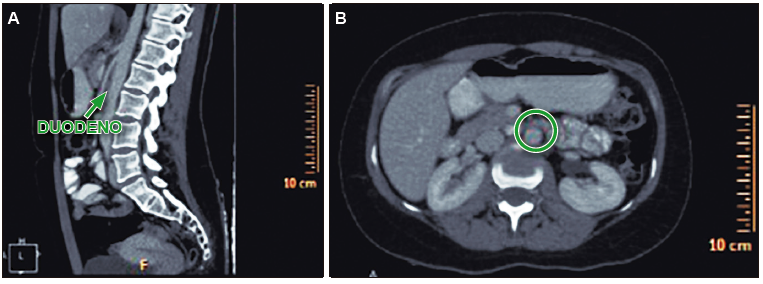

Figura 2. En el corte sagital (A) y axial (B) de la TC de abdomen con contraste se

observa el estrechamiento del compás aorto-mesentérico que comprime la tercera porción duodena